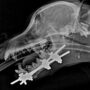

George had to have four hours of surgery to rebuild his jaw using pins and an external metal cage.